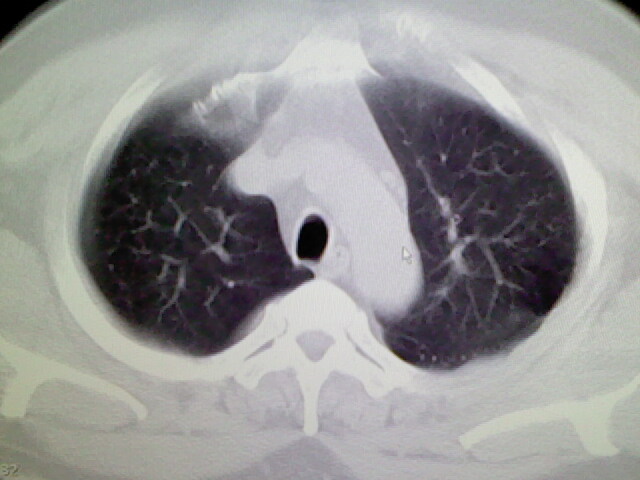

左肺上叶舌段少许炎症。

肺纹理分布较均匀,暂不提示肺梗塞

左上肺局限片状透光度增强区,肺纹理稀少,可考虑局限性肺气肿。